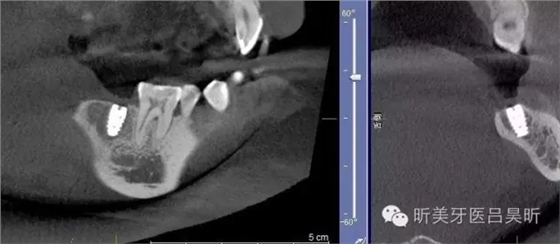

本次病例介紹一例簡單種植,根據(jù)患者術(shù)前CBCT,因牙槽骨的形態(tài)特殊性,會為種植帶來一定的難度,對于經(jīng)驗豐富的醫(yī)生可能會掌控自如,但在操作上的風(fēng)險會增加,通過導(dǎo)板技術(shù)可減少風(fēng)險發(fā)生并能實現(xiàn)精準(zhǔn)定位。

術(shù)前CBCT截圖,垂直骨量似乎感覺良好

可見種植位點(diǎn)舌側(cè)區(qū)凹陷,牙槽骨上部舌傾明顯。

擬定種植三維方向

術(shù)后CBCT 檢查,植入位點(diǎn)良好,與術(shù)前設(shè)計基本一致,并實現(xiàn)安全植入。